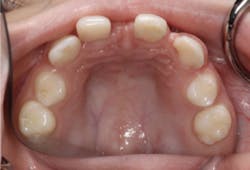

Before a treatment plan can be developed, it is crucial to make an accurate dental diagnosis. Although the patient was only nine years old, it was necessary to outline diagnostic protocols to thoroughly evaluate and diagnose. We started with a complete exam, diagnostic photographs, and study casts mounted in centric relation (figures 9a and 9b). Through these records, we were able to determine the patient’s ideal tooth position to satisfy her esthetic goals. We discussed treatment options on how to achieve these results with both the patient and the parents (figure 10).